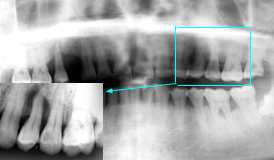

| 初診時 パノラマ | 同 パノラマ |

| 全体に軽度な骨吸収が認められる 27歳 男性 |

上下左右第一大臼歯の骨欠損が著明 |

初診時口腔内およびX線所見:

口腔内清掃状態は比較的良好で歯石沈着は比較的少ないが、全体に軽度な歯槽骨吸収

が認められる。その中で、|2の骨吸収は根尖部に至るほか、上下左右第一大臼歯に

中程度以上の骨欠損が認められる。

処置および経過:

|2咬合のたびに激しく動揺し、まるで“のれん”の様な状態で、保存の見込みは全く

ないように思われた。しかし、根管治療には問題なく周囲への影響がなさそうなことと、抜歯後

の補綴による隣在歯への影響を考慮して、除石と咬合調整を行って当分はそのまま使うことと

した。

初期カリエスの治療と伴に、スケーリング&ルートプレーニングを施行してメインテナンスに移行。

考察:

年齢的には、典型的な若年性歯周疾患とは言い難いが、特徴とされる上下左右第一大臼歯に

著明な骨欠損が認められる。反面、上下左右の中切歯には著明な骨欠損は見当らない。

上下左右中切歯および第一大臼歯に著明な骨欠損が認められる理由として、一般にはその